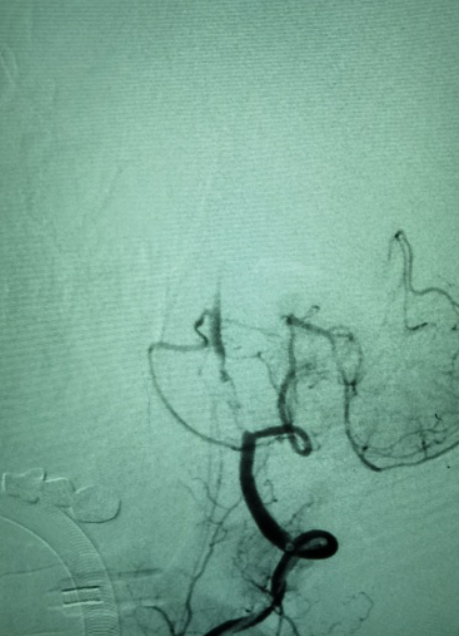

入院颅脑MRI+MRA可见右侧小脑新发梗死,基底动脉中段显影欠佳。

全脑血管造影提示右椎纤细,颅内段不显影。左椎颅内段发出小脑后下动脉已远闭塞,但部分血管吻合,使左椎V4远端浅淡显影。

前循环造影提示后交通开放,基底动脉逆向显影,基底动脉中下段血管床未显影。